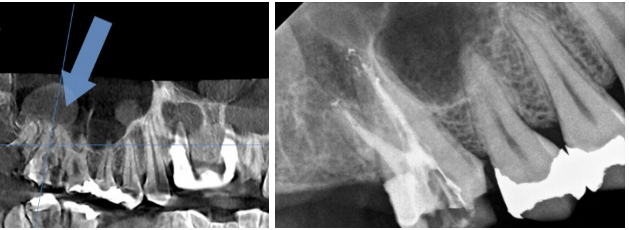

충치를 제거한 뒤, 신경관에 접근하는 치수강을 열어보았습니다.

오른쪽 치아의 치수강 내부는 깨끗했지만, 왼쪽 치아는 내부 오염이 심한 상태였습니다.

이처럼 치수강 오염이 심한 경우, 충치가 치아 신경이 지나가는 뿌리까지 도달했을 가능성이 높습니다.

따라서 치료가 잘 이루어지더라도 치아의 수명이 길지 않은 경우가 많습니다.

왼쪽 치아의 CT 결과에서도 뿌리 아래쪽에 큰 염증이 확인되었습니다.

환자분께 치아 상태와 예후를 자세히 설명드린 후, 치아 상태가 좋지 않아 발치를 원하신 덕분에 임플란트 시술을 진행하기로 결정하였습니다.

오른쪽 사진에서 보이는 다른 치아들은 신경치료로 치료를 마무리했습니다.

이처럼 비슷한 통증을 느끼더라도, 충치의 깊이와 진행 정도에 따라 치료 결과는 달라질 수 있습니다.